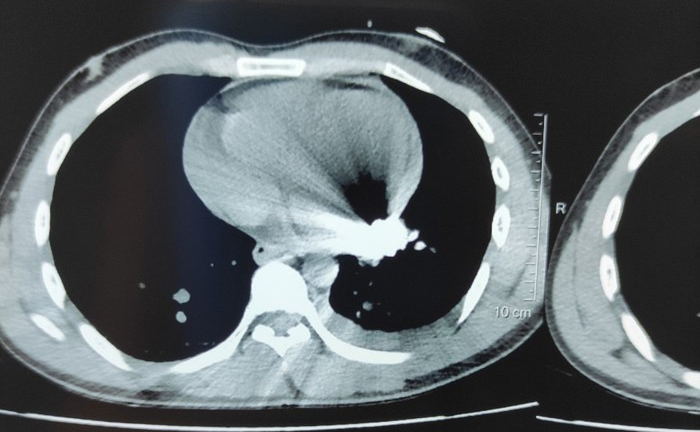

Đang đốt rác, anh T. gục xuống sau tiếng nổ, sau đó bác sĩ lấy ra một đầu đạn từ tim nạn nhân.

Nhập viện trong tình trạng huyết áp không đo được, sau 4 giờ phẫu thuật, nam bảo vệ được các bác sĩ Bệnh viện Đa khoa Đồng Nai cứu sống